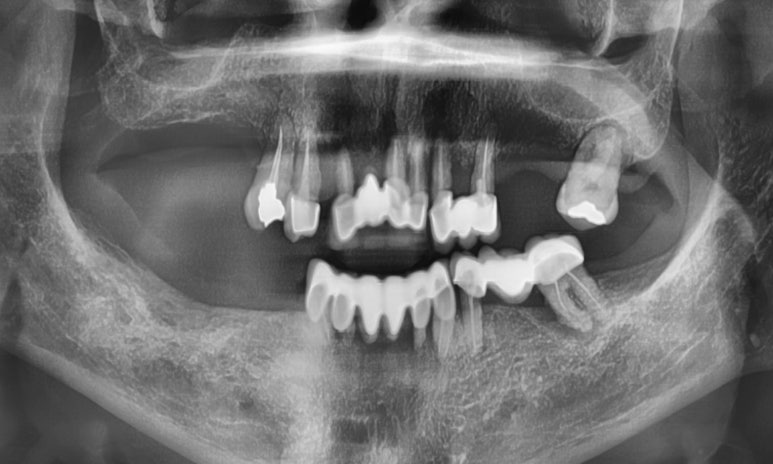

처음 치료전 상태

진짜 저 치아들을 다 뽑아야해? 라고 생각하실 수 있겠지만

동영상을 보시면 기존 해외 다른치과에서 한

위 아래 브릿지가 엄청 흔들려서 (=브릿지 아래 치아뿌리가 흔들리는 것)

발치를 해야할 수 밖에 없다는 것을 아실 겁니다.

최대한 살릴 수 있는 치아는 살리기 위해서

위에는 치아를 살리기 힘들었기 때문에 다 뽑고 전체 인플란트를 하고

아래쪽 같은 경우는 살릴 수 있는 치아는 냅두고

나머지 부분만 임플란트를 하기로 하였습니다